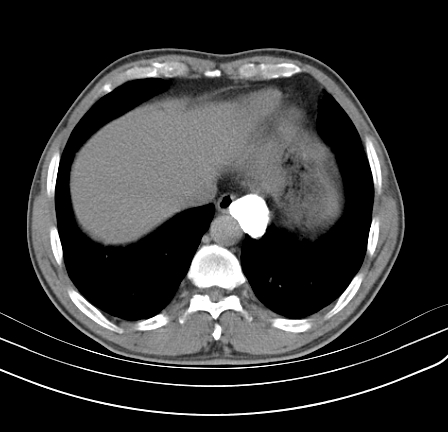

以下是引用影像孺子牛在2009-5-20 23:18:00的发言:[br]左侧后心膈角处类椭圆形钙化灶,最常见的是淋巴结钙化,但太大了不支持,其它如食管囊肿钙化、实性畸胆瘤等。何东西钙化真不好定。

以下是引用zbp537在2009-5-20 20:52:00的发言:[br]钙化灶,来源不好说。